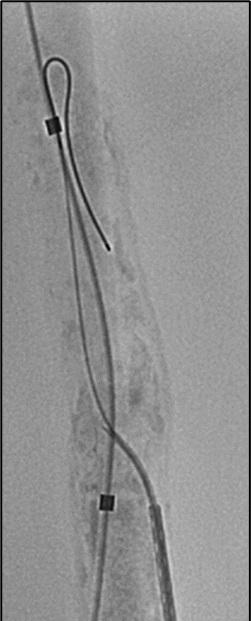

There are some significant challenges with running a large, multicentre randomised controlled trial (RCT). So far, we have encountered a number of subjects that present with pathologies which are not typical for textbook aortic dissections and thus pose challenges

to inclusion. The inclusion period is relatively long after symptoms occurrence and this might lead to selection bias if criteria are not adhered to and the intent of the trial followed. Being a strategy-based trial (like the IMPROVE trial for ruptured abdominal aortic aneurysm [AAA]) it is important that investigator truly attempt to include and randomise patients before evaluating the applicability of a TEVAR procedure or the trial might be biased towards “cherry picking” only anatomically appealing candidates which might skew the trial in favour

of TEVAR. The strategy-based setup will likely lead to a number of crossover cases post randomisation but will obviously add the benefit of identifying what the applicability of TEVAR actually is.